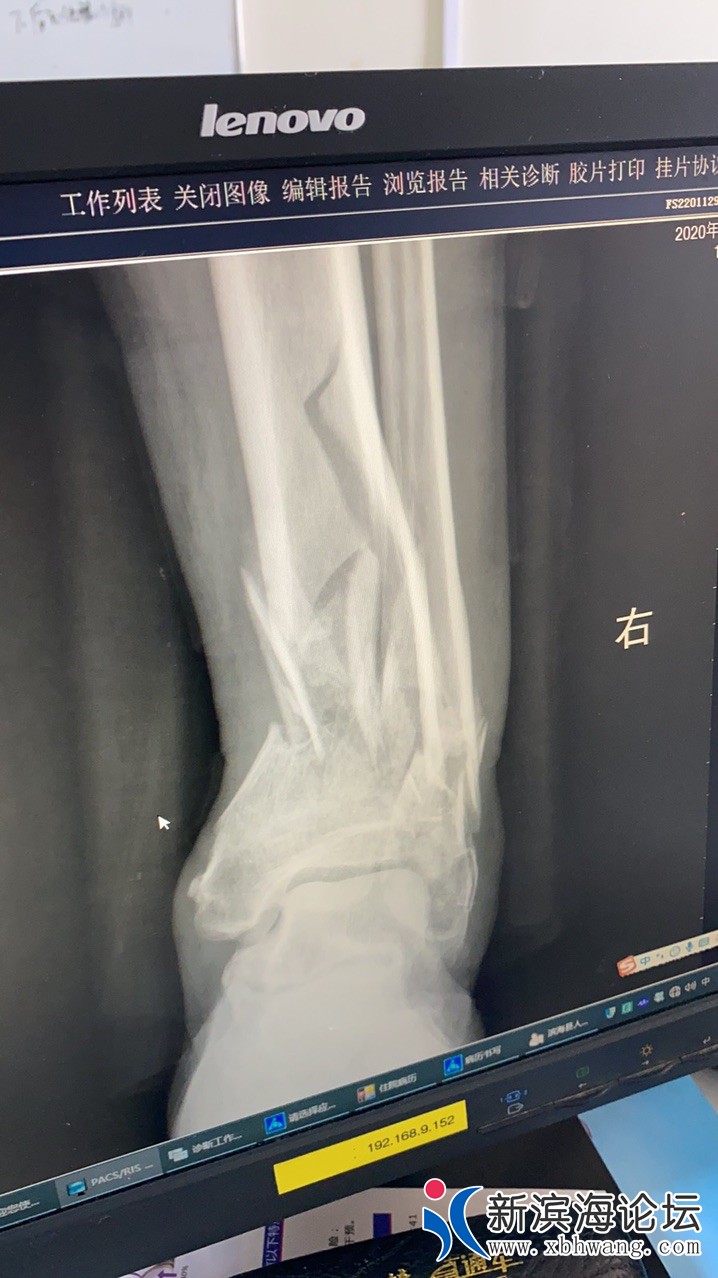

2020年11月15日早晨07:30分左右,我父亲骑着电动车由西往东正常直行,肇事者驾驶三轮摩托车由南往北转弯向东与我父亲发生了交通事故(案发地点:滨淮镇沈滩三中桥)我父亲摔倒在地,肇事者弃车离去,目击者阻拦无果!随即我父亲打电话给我,我带着我妈去往目的地,到了目的地看见我父亲坐在案发点,手摸着脚踝,随即我妈拨打了110-120!到了医院检查、脚踝粉碎性骨折,肇事者至今没有下落,望知情的朋友们  联系一下我!谢谢您!陈:15722545328